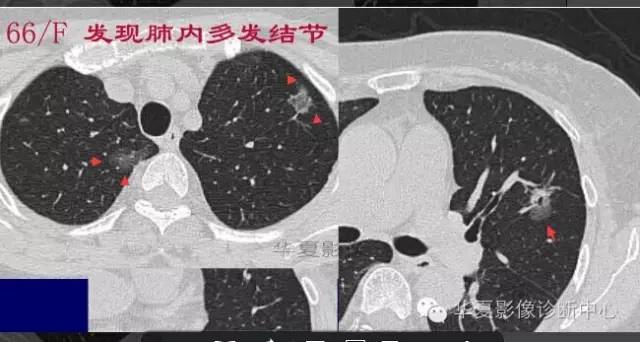

第一步:判断是否GGO

第二步:判断是否肿瘤

第三步:看边缘及内部征象

磨玻璃结节良恶性影像分析策略 混合型,边界清楚、分叶征,考虑肺癌

磨玻璃结节良恶性影像分析策略 磨玻璃结节良恶性影像分析策略磨玻璃结节良恶性影像分析策略 其中血管显示清楚,GGO

边界清楚,分叶征,空泡征